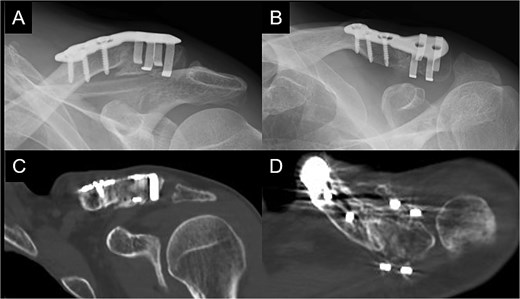

A 66-year-old man presented with left shoulder pain after falling. A Neer Type IIB fracture of the distal clavicle with significant displacement was revealed on radiographs (Fig. 1); however, owing to severe aortic valve stenosis and heart failure, the patient was deemed unfit for surgery. The patient underwent conservative treatment for distal clavicle fracture for 5 months; however, the pain in the left shoulder persisted, and significant skin protrusion caused by a displaced bone fragment was noted. No findings suggestive of neurovascular injury were observed. Radiography and computed tomography (CT) examinations revealed fracture displacement progression (Fig. 2A–C). After undergoing aortic valve replacement 3 months postinjury, the cardiac function of the patient improved and surgery was performed to treat the distal clavicle nonunion.

Radiographs captured immediately after injury show a fracture of the left distal clavicle with displacement.

Radiographs (A and B) and CT scans (C and D) captured after 5 months of conservative treatment show that the displacement has progressed.